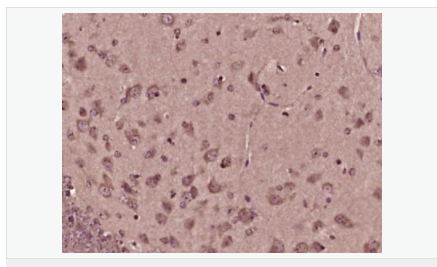

| 產品應用 | WB=1:500-2000 ELISA=1:5000-10000 IHC-P=1:100-500 IHC-F=1:100-500 IF=1:100-500 (石蠟切片需做抗原修復) not yet tested in other applications. optimal dilutions/concentrations should be determined by the end user. |

| 產品介紹 | BM88 is a 149 amino acid protein that belongs to the CEND1 familly. Involved in neuroblastoma cell differentiation, BM88 is a single-pass type IV membrane protein that is neuron specific. It is suggested that BM88 forms a dimer of two identical polypeptides linked by disulfide bridges. BM88 has a central proline-rich region containing four PxxP motifs, which typically bind SRC homology-3 (SH3) domains, as well as a putative C-terminal transmembrane region, and several potential sites for N-glycosylation, myristoylation and phosphorylation. It is also suggested that a novel signaling mechanism exists by which BM88 interferes with calcium release from inositol 1,4,5-trisphosphate-sensitive stores and exerts anti-proliferative and anti-apoptotic functions. BM88 is an important molecular target for HDAC inhibition, and transcription of BM88 is induced by trichostatin-A. Function: CEND1 is a neuron-specific protein. The similar protein in pig enhances neuroblastoma cell differentiation in vitro and may be involved in neuronal differentiation in vivo. Multiple pseudogenes have been reported for this gene. Subunit: Homodimer Subcellular Location: Membrane; Single-pass type IV membrane protein. Tissue Specificity: Neuron specific. Similarity: Belongs to the CEND1 family. SWISS: Q8N111 Gene ID: 51286 Database links: Entrez Gene: 51286 Human Entrez Gene: 57754 Mouse Omim: 608213 Human SwissProt: Q8N111 Human SwissProt: Q9JKC6 Mouse Unigene: 22140 Human Unigene: 87027 Mouse Unigene: 64460 Rat Important Note: This product as supplied is intended for research use only, not for use in human, therapeutic or diagnostic applications. |